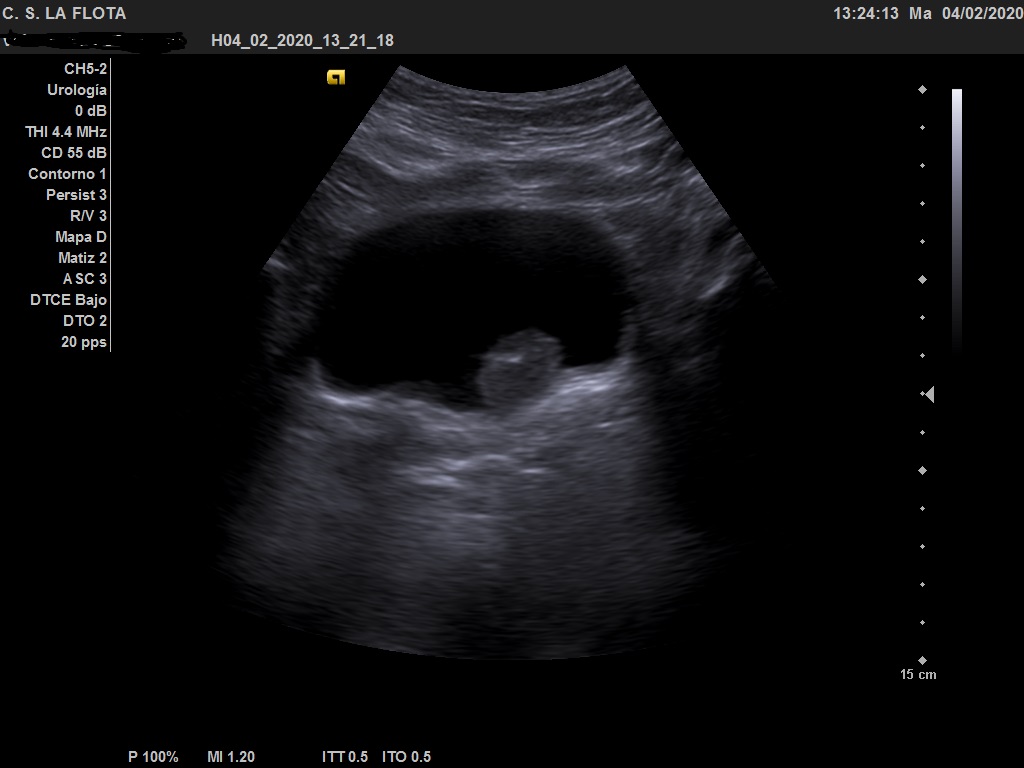

Ecografía clínica: riñones de tamaño y morfología normal, con buena diferenciación corticomedular y sin dilatacion de vias. En vejiga lesión polipoidea  de 25*18 mml.